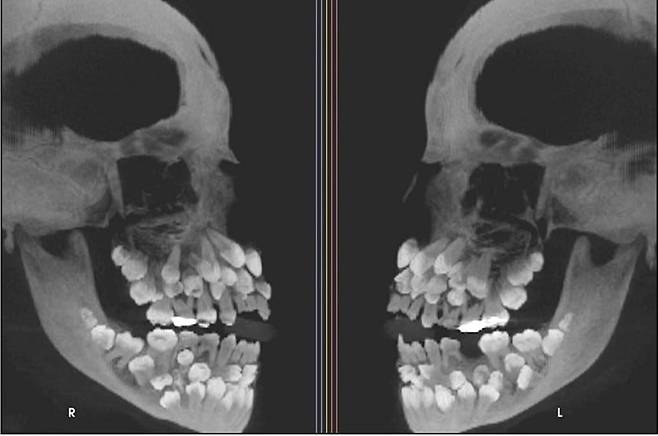

최근 VN익스프레스 등에 따르면 브라질에 사는 11세 소녀의 구강 엑스레이 결과 입 안에서 유치 18개와 영구치 32개, 과잉치 31개 등 총 81개 치아가 발견됐다.

이는 ‘다발성 과잉치증(multiple hyperdontia)’으로 일반적으로 성인 기준 32개인 정상 치아 수를 넘는 추가 치아가 다수 존재하는 선천성 이상이다. 보통은 1~2개의 과잉치가 발견되며, 이번처럼 30개가 넘는 과잉치가 확인된 사례는 전 세계적으로도 매우 드물다.

연구팀은 정밀 영상 검사를 통해 치아의 정확한 위치를 파악했다. 또 과잉치증이 유전 질환과 연관된 것은 아닌지 확인하기 위해 관련 유전자 검사도 함께 진행했다.

과잉치는 잇몸 속에 깊이 묻혀 있거나 정상 치아와 형태가 유사해 정확한 구분이 쉽지 않다. 무작정 발치할 경우 턱뼈 손상 우려도 있어 치료가 쉽지 않다.